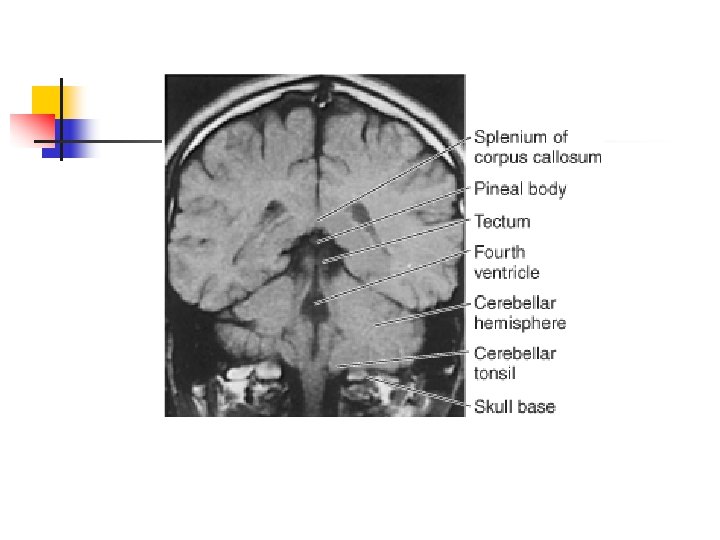

Cerebellum n n n The cerebellum is located behind the dorsal aspect of the pons and the medulla. It is separated from the occipital lobe by the tentorium and fills most of the posterior fossa. A midline portion, the vermis, separates two lateral lobes, or cerebellar hemispheres. The cerebellum consists of the cerebellar cortex and the underlying cerebellar white matter Four paired deep cerebellar nuclei are located within the white matter of the cerebellum Because of the location of the fourth ventricle, ventral to the cerebellum, mass lesions or swelling of the cerebellum can cause obstructive hydrocephalus.